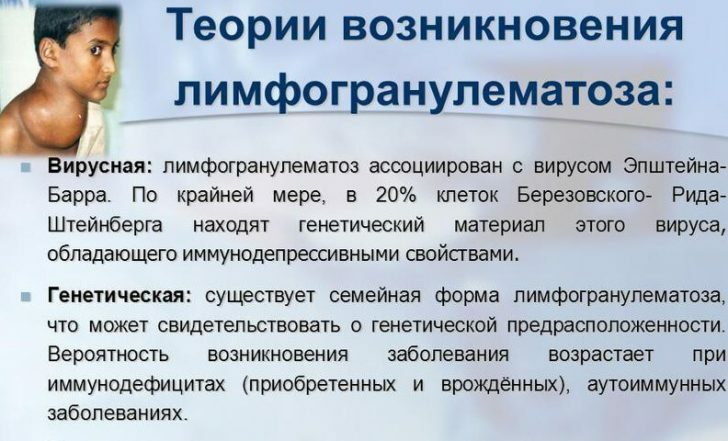

Микропрепараты: Лимфогранулематоз и Нодулярный Склероз

Раздел: Секреты мастерства